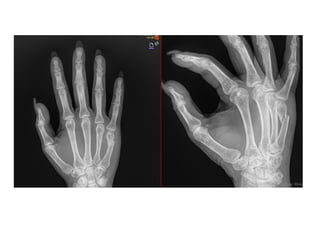

NOMBRE:LOPEZ GOMEZ CECILIA

NSS:7623610167 1F1961OR

URGENCIAS A

Edad: 64 AÑOS

Comorbilidades: NINGUNA

Fecha de la lesión: 20/09/25

Mecanismo de lesión: CAIDA DE PROPIO PLANO DE SUSTENTACION

Laboratorios: DENTRO DE NORMALIDAD

Valoraciones: NA

Diagnósticos: FRACTURA DIAFISIARIA DE 4TO MTC Y FRACTURA DE LA BASE DEL 5TO MTC MANO IZQUIERDA

Cirugía Proyectada: REDUCCION CERRADA Y FIJACION PERCUTANEA CON CLAVILLOS K A 4TO Y 5TO MTC MANO IZQUIERDA

Material OSS Solicitado: CLAVILLOS K

NOMBRE:LOPEZ GOMEZ CECILIA NSS:76236101671F1961OR URGENCIAS A Edad: 64 AÑOS Comorbilidades: NINGUNA Fecha de la lesión: 20/09/25 Mecanismo de lesión: CAIDA DE PROPIO PLANO DE SUSTENTACION Laboratorios: DENTRO DE NORMALIDAD Valoraciones: NA Diagnósticos: FRACTURA DIAFISIARIA DE 4TO MTC Y FRACTURA DE LA BASE DEL 5TO MTC MANO IZQUIERDA Cirugía Proyectada: REDUCCION CERRADA Y FIJACION PERCUTANEA CON CLAVILLOS K A 4TO Y 5TO MTC MANO IZQUIERDA Material OSS Solicitado: CLAVILLOS K